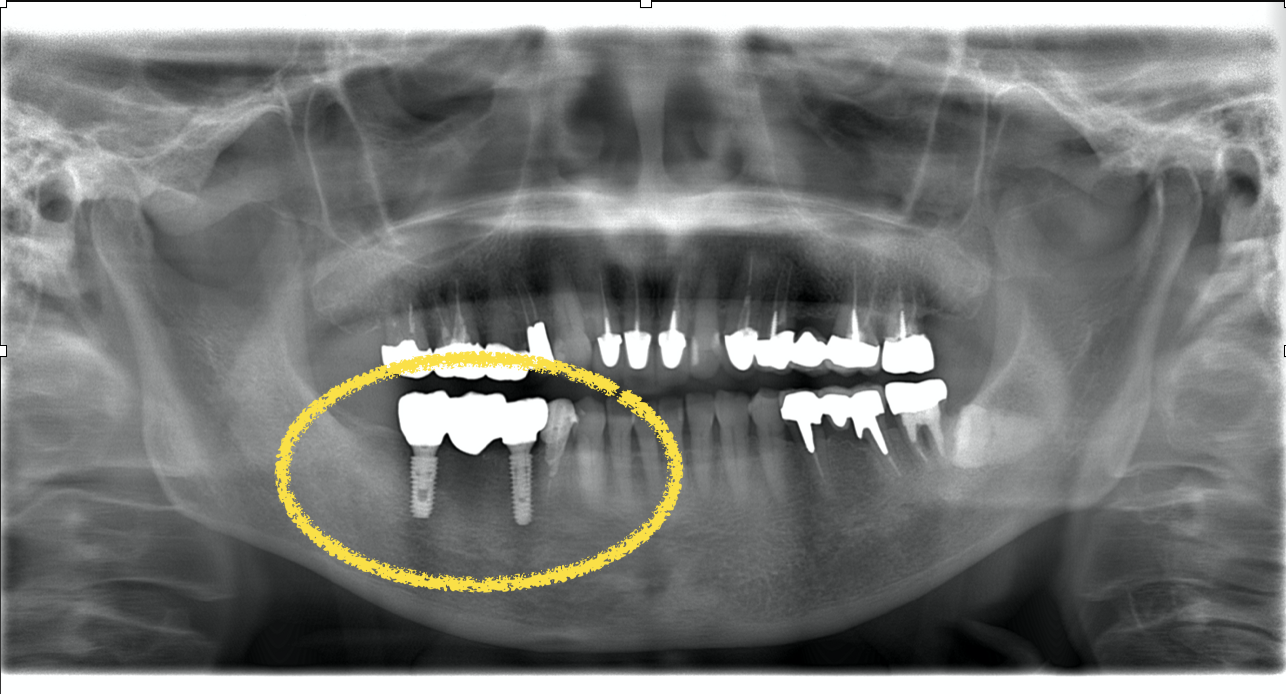

このケースでは手術後約4ヶ月でインプラント部に歯が入りました。黄色い枠線で囲ってある3本の歯がインプラントの歯です(ジルコニア)。

黄色の枠の中の白いものがジルコニアブリッジです。綺麗に入りました。